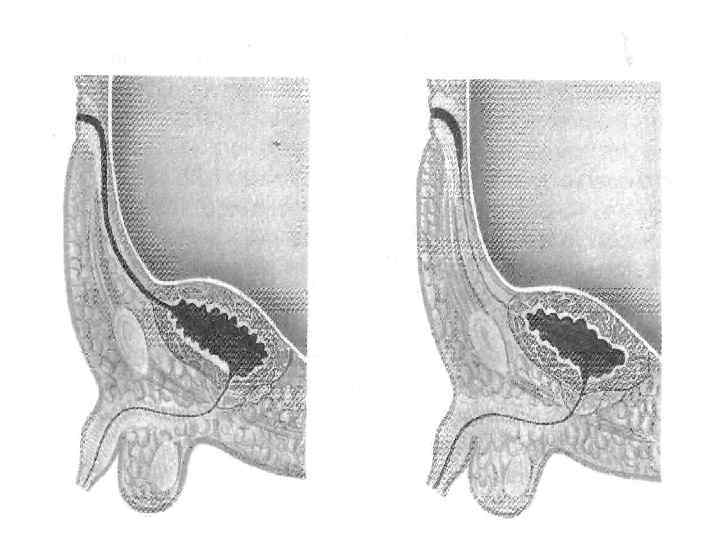

АНОМАЛИИ РАЗВИТИЯ МОЧЕПОЛОВОЙ СИСТЕМЫ

Сосудистая ножка почки

Иссечение кисты и обработка внутренней ее выстилки